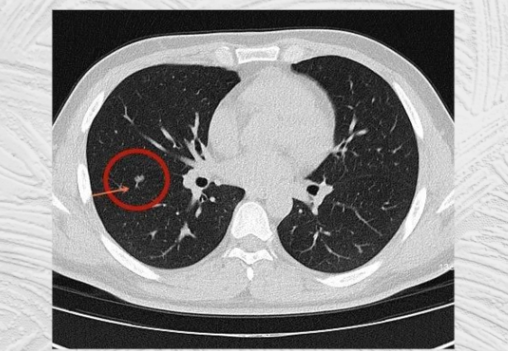

口罩事件之后,很多人患上了肺结节,而且很多还患上了毛玻璃结节(被认为是癌变率极高的一种类型),目前对于肺结节而言,常规的抗生素和激素疗法治疗效果非常有限。手术治疗肺结节,效果“立竿见影”,但是对自身体的脏腑损伤比较大,很多情况下留下难以治愈的后遗症,如肺部刺痛、荨麻疹等,最重要的是,手术无法改善身体大环境,切除之后还复发,而且对于高风险的肺结节手术治疗有造成转移风险增大。

那么肺结节怎么治疗呢?有没有什么办法能治疗肺结节呢?既然很按现代科学的角度难以得到理想的答案,我们可以从中医药及天然抗癌抗肿瘤成分找到答案。传统中药灵芝和二氢槲皮素是两位明星级的天然抗结节原料与成分。